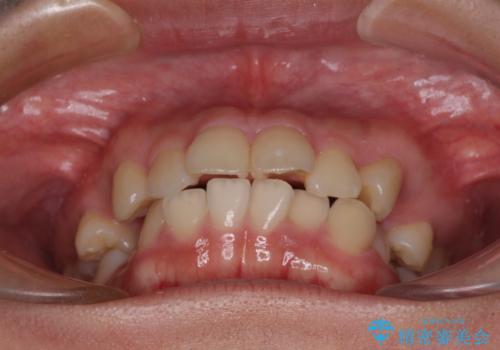

- 口元の閉じにくさを気にして来院された患者様です。

地元で矯正治療を始める予定で上顎左右第1小臼歯2本を抜歯したものの、その後転居したため治療が滞っているとのことでした。

上下ともに歯列が前方に突出していたため、上下左右の第一小臼歯4本を抜去する方針(既に上顎は抜歯されています)で、ワイヤー装置による矯正治療を行うこととしました。